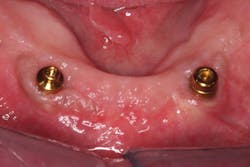

Since a minimum of four implants are in place, it is very difficult to feel a "squish." Instead, I line the inside of the denture with light-body impression material, seat the denture on the abutments, and remove the denture after the material sets. Probe the impression material in multiple locations (figures 16–18). If probing is shallow and consistent through the denture, a reline is not indicated. If any areas are deeper, a reline is indicated. Note: The attachments are clearly visible in Figures 17 and 18, but often a thin layer of impression material will cover them.